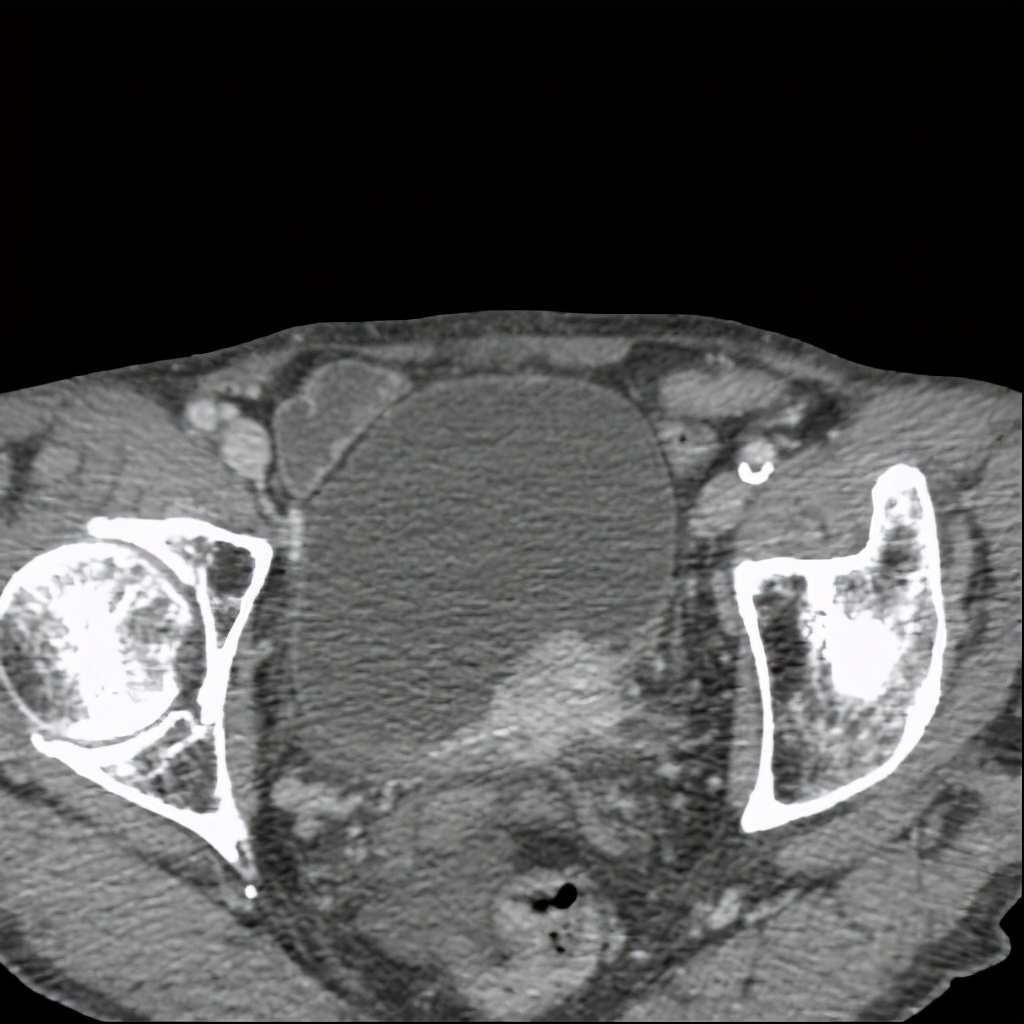

上图所示:63岁男患,有脑出血术后病史,长期卧床,近期存在小便*禁失**。CT尿路造影检查示膀胱壁增厚,存在膀胱憩室,伴有双肾积水,双侧输尿管扩张。考虑存在神经源性膀胱可能